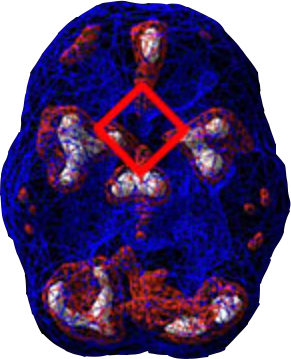

PTSD BRAINS WORK DIFFERENTLY

People who are suffering with posttraumatic stress disorder often have abnormal brain function that causes overactivity in multiple areas of the brain. On a PTSD brain scan, abnormally high activity is commonly seen in specific brain regions: the deep limbic area, basal ganglia, and anterior cingulate gyrus, a brain region that is involved with shifting attention or getting stuck. In addition to being a very useful tool for determining a correct diagnosis, brain SPECT imaging helps PTSD patients in other ways too, including:

Healthy Brain

Scan

PTSD Brain

SPECT (single photon emission computed tomography) is a nuclear medicine study that evaluates activity (blood flow) in the brain. Basically, it shows three things: healthy activity, too little activity, or too much activity in brain structures. In a healthy “active” brain scan, blue represents average blood flow and red and white represent increasingly higher levels of blood flow. In the healthy scan on the top right, the most active area is the cerebellum, located in the back/bottom part of the brain, and this is normal to see. The PTSD scan below it reveals high activity in areas of the brain called the deep limbic area, basal ganglia, and anterior cingulate gyrus in a “diamond pattern,” which is a classic finding in cases of posttraumatic stress disorder. There are significant differences in the SPECT scans of PTSD compared to healthy scans. Other types of brain imaging, such as a magnetic resonance imaging study show the anatomy of a brain structure, but not how well it functions.